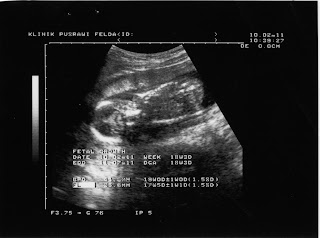

ni la antara pic scan during pregnant...from week 10 till week 25 only coz week 26 i'm giving birth...hehehe...yg tu kte smbung part III okey...

weeks 18